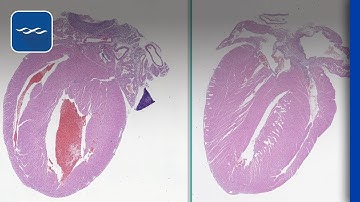

Digital Pathology Workflow